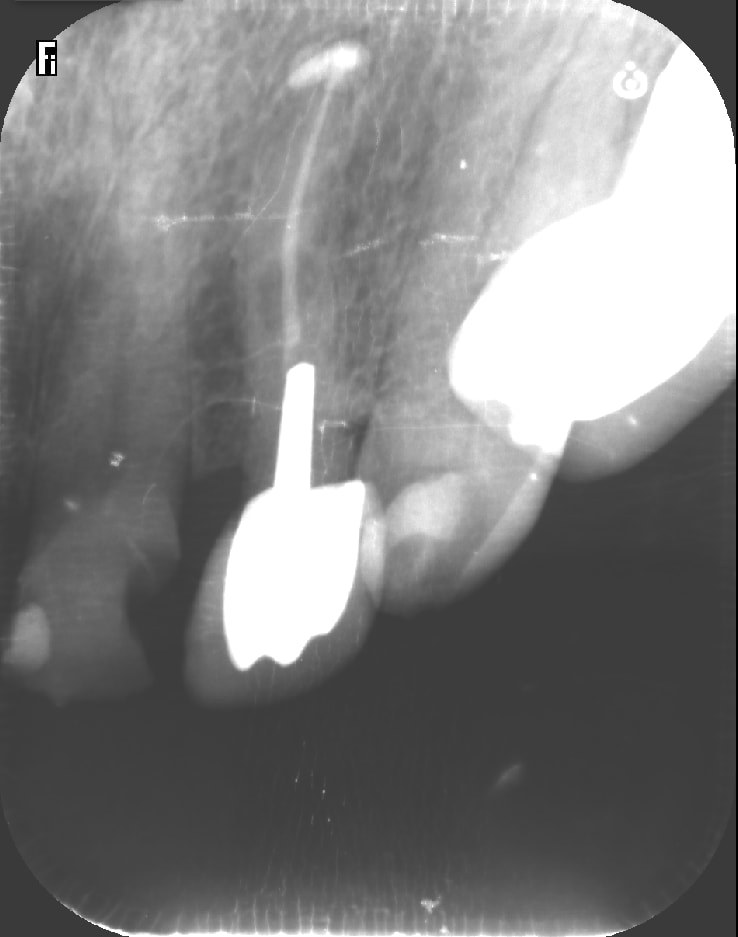

Dernier cas de ERI faite entre midi et deux. Au niveau historique, abcès 15 mars 2019, je retraite et je suis plutôt content ( merci au passage chicot qui m'a appris l'endo) et on temporise. L'image radio est toujours présente plus de 6 mois après avec fistule qui va et qui vient. Devis implant trop cher et donc je propose l'ERI. La suite en image. Je croise les doigts. J'ai positionné la dent un peu plus haut pour faire un style d'élongation coronaire, je ne sais pas si j'ai bien fait car la dent est quand meme plus mobile que bien enfoncée dans son alvéole...à suivre

et bien sur merci à enlay qui nous apprend l'ERI ( entre autre)!

Vu que tu as eu l'occasion de voir la racine de près, tu n'as pas vu une fêlure/fracture ? L'image latérale m'évoque ça en première intention surtout si ça guérit pas , comme ta reprise semble top.

merci. non pas vu de fracture. J'ai pensé plus à un canal latéral. La pro etant la depuis un an je pense que j'aurais eu une évolution de l'image osseuse tout autour de la dent+ descelllement. Comme je peux plus mettre les loupes avec ces visières de merde, je suis peut être passé à coté aussi... à suivre